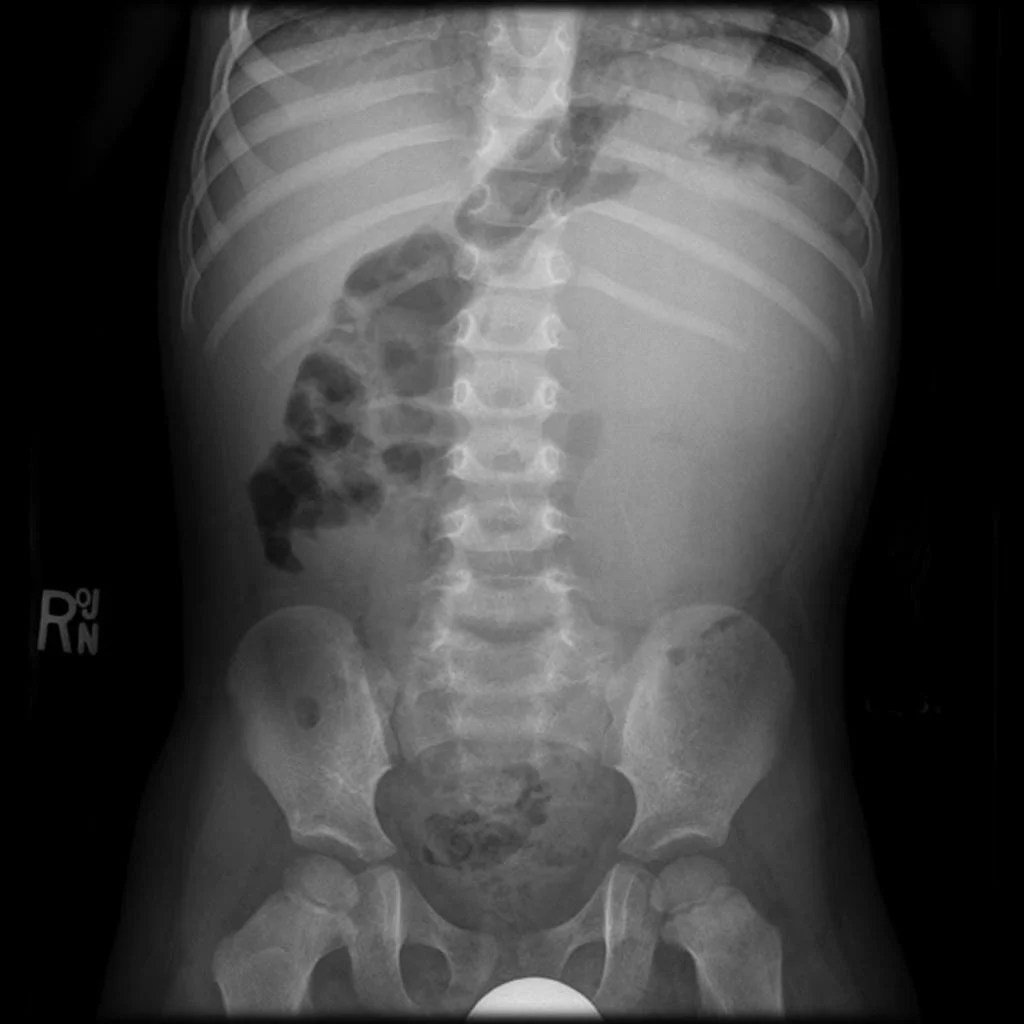

Moderate stool burden with nonobstructive bowel gas pattern What Does Stool Look Like On X Ray The valvulae conniventes (also called plicae circulares) are. • on conventional radiographs, there are one or two persistently dilated loops of small bowel. Generally the small bowel lies centrally within the abdomen. Excessive stool burden can be. It is seen as speckled material along the periphery of the abdomen where the colon is located. Gas is either swallowed or formed. What Does Stool Look Like On X Ray.